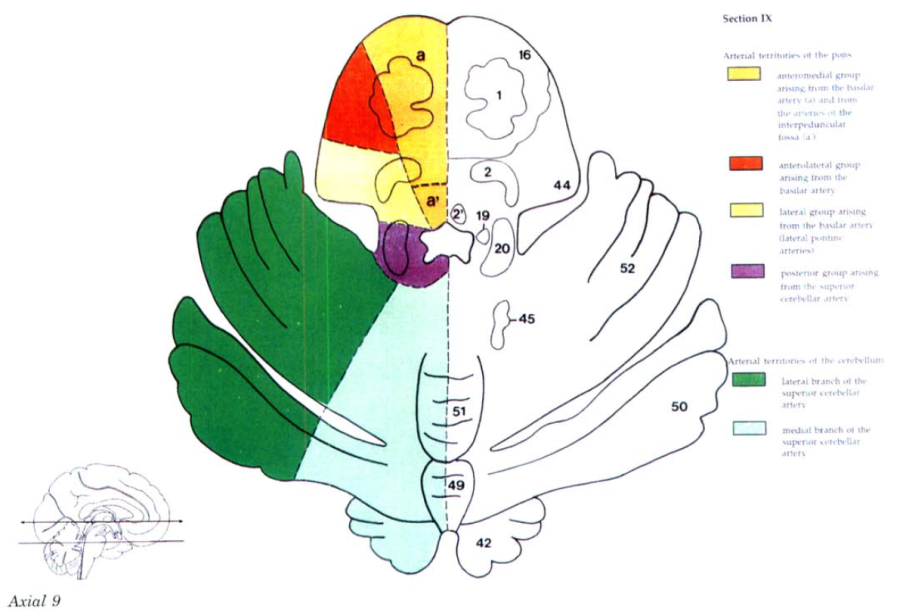

Cerebral vascular territories

Brainstem